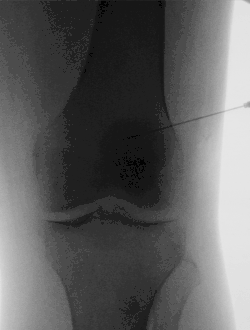

Die Arthrographie ist die Darstellung des Gelenkinneren mit Kontrastmittel als radiologische Untersuchungsmethode von Gelenken. Bevor bildgebende Verfahren der Sonographie, der Magnetresonanztomographie und der Computertomographie zur Verfügung standen, war die Arthrographie die einzige Möglichkeit, Weichteilstrukturen der Gelenke mittels einer Röntgenuntersuchung darzustellen. Dazu wird ein Kontrastmittel in das Gelenk gespritzt. Anschließend werden aus verschiedenen Winkeln Röntgenaufnahmen angefertigt. Durch das Kontrastmittel sind nun auch die nichtknochigen Bestandteile des Gelenks auf dem Röntgenbild beurteilbar.

Gleichzeitig sind mit der Entwicklung der Magnetresonanztomographie und der Computertomographie neue Einsatzgebiete für die Arthrographie entstanden. Hierbei dient die Kontrastmittelinjektion in das Gelenk der Entfaltung der Gelenkkapsel und somit der besseren Beurteilbarkeit der ansonsten eng aufeinanderliegenden Weichteilstrukturen. Des Weiteren lassen sich manche Verletzungen des Knorpels, der Gelenkscheiben (Menisci), der Gelenkkapsel und der Gelenkbänder nur mit Hilfe einer Kontrastmittelinjektion sicher beurteilen. Insbesondere in der Diagnostik des Schultergelenks und der Handwurzel ist die Arthrographie mit anschließender Kernspintomographie oder Computertomographie wieder ein Standardverfahren geworden.